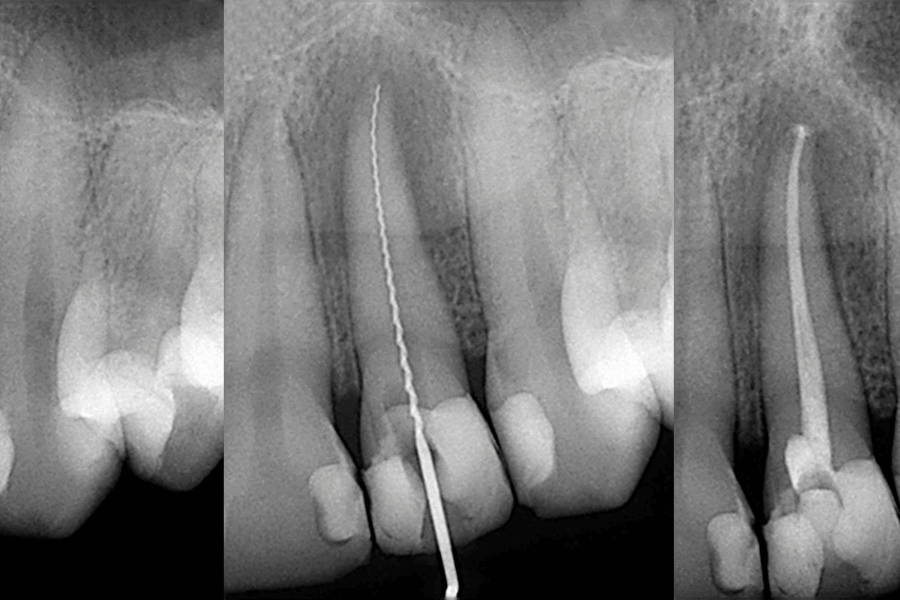

Se realiza una endodoncia dental cuando el nervio del diente se ve afectado y un empaste no es suficiente para conservarlo. Comúnmente se conoce esto como «matar el nervio del diente».

Es un tratamiento indoloro que consiste en desinfectan los conductos de la raíz del diente, evitando que la infección se propague a la sangre y a otras partes del cuerpo.La causa principal por la que se suele realizar este tratamiento es por una caries en etapa avanzada, pero hay otras razones que nos pueden llevar a necesitar este tratamiento:

- Endodoncias unirradiculares: Se realiza en dientes con una sola raíz y por lo tanto un solo conducto radicular. Esto ocurre en, los incisivos centrales, los laterales y los caninos, tanto superiores como inferiores. También ocurre esto con los primeros y segundos premolares inferiores.

- Endodoncias birradiculares: Se hacen en dientes con dos conductos radiculares como, por ejemplo, los molares inferiores en su raíz mesial y los segundos premolares superiores, estos solo presentan una raíz, pero suelen tener dos conductos radiculares.

- Endodoncias multirradiculares: Se realizan cuando el diente cuenta con tres o más conductos radiculares. Los molares superiores es bastante común que presenten un total de cuatro conductos radiculares.